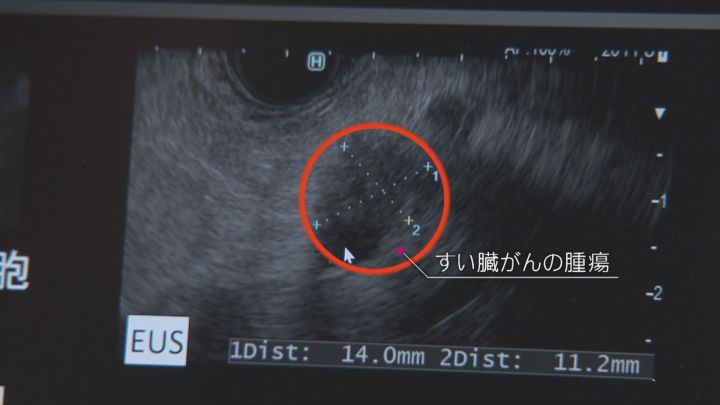

腹部エコー検査では、肝臓、腎臓、胆のうなど多くの臓器を見ることができる。中でも期待されているのが、「すい臓がん」の早期発見だ。

「胃がんのピロリ菌とか、肝臓がんのC型肝炎とか、(すい臓がんは)原因がはっきり1対1でわかっていない。進行したすい臓がんは誰でも診断できますけど、早期すい臓がんは、CTなどで腫瘍として認識できないようなものを探していかなければいけないので、非常に見つけにくいです」